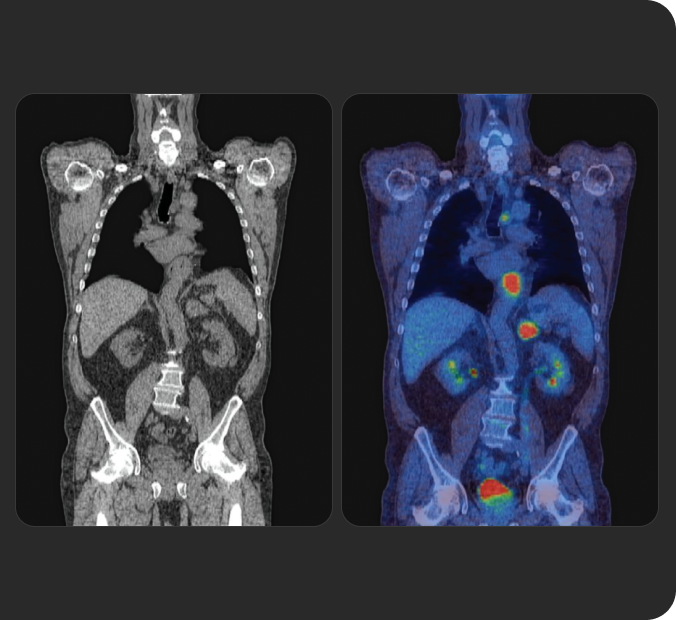

Tratar o que se vê

Os radioligandos podem ter uma finalidade e aplicação diagnóstica e terapêutica, permitindo uma abordagem teranóstica, que pode ser traduzida pela afirmação "tratar o que se vê e ver o se trata" (do inglês "see what you treat and treat what you see"). 1b 4 5

A ciência

RLT representa uma evolução em direção ao tratamento de precisão

RLT é uma abordagem de medicina de precisão que reconhece e trata diretamente a doença, com um foco particular nos cancros avançados.

Recorrendo ao poder dos átomos radioativos, RLT é capaz de dirigir radiação às células-alvo em qualquer parte do corpo.7a 8a